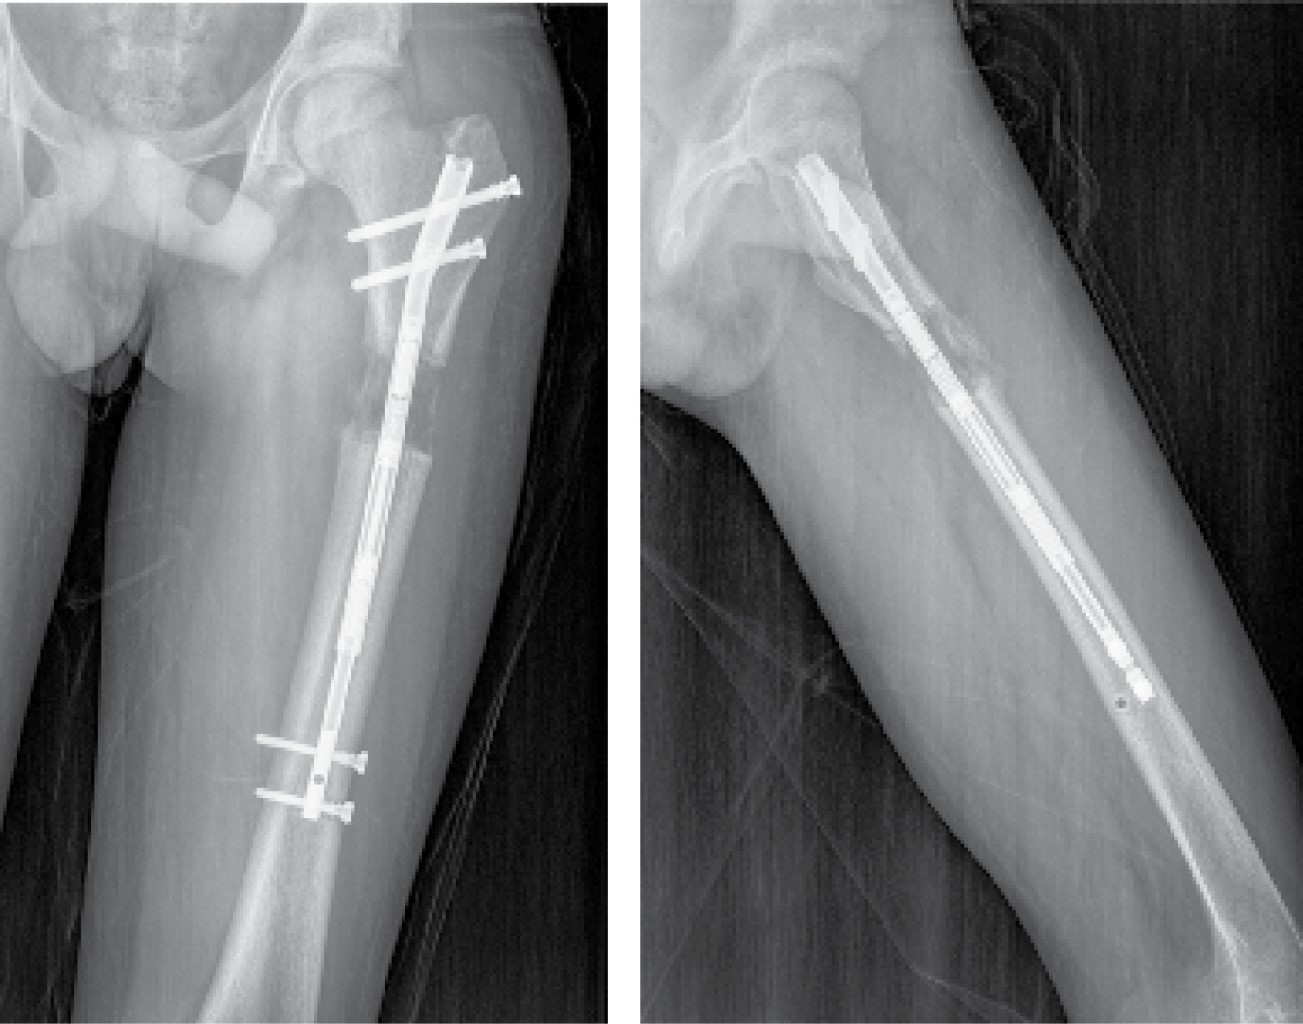

Todos los pacientes fueron instruidos para el correcto funcionamiento del dispositivo y comenzaron el alargamiento femoral a la semana de la intervención en torno a 1 mm/día. El primer control radiográfico se realizó a los siete-10 días de la intervención y posteriormente, de manera sucesiva, cada dos semanas hasta el final del alargamiento (Figura 3), cuantificando el mismo en cada revisión. Después se realizó un seguimiento mensual durante la fase de consolidación (Figura 4), la cual comprende desde el final del alargamiento femoral hasta la consolidación ósea de la zona alargada (Figura 5). Por último, se realizaron controles a los seis meses, al año y a los dos años de la cirugía.

La dismetría prequirúrgica medida fue de 38 ± 2.7 mm. El alargamiento final medido en las radiografías postoperatorias fue de 41 ± 7.5 mm. La precisión media fue de 108% y la tasa de distracción de 0.9 ± 0.4 mm/día. El índice de distracción medido fue de 13.9 ± 5.1 días/cm y el índice de consolidación de 26.6 ± 9.1 días/cm. El tiempo medio de distracción fue de 57.6 ± 25.9 días. Los datos por pacientes quedan reflejados en la Tabla 2.

Figura 3

Figura 4